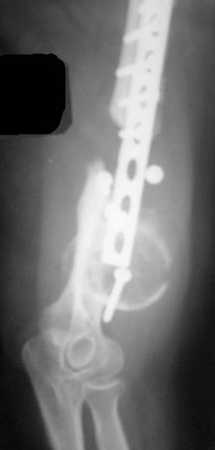

Anatoly F. Lazarev 23 Февраль 2008, 01:04

Типичная положительная ситуация для интрамедуллярного остеосинтеза с

использованием опорного металлокаркаса для компенсации дефекта.

Послеоперационное ведение активное или агрессивно-активное. Каркасы

можно заказать в МАТИ.

Рентгеновская версия реконструкции. хронология:

после операции, 2 мес. после операции, через 1 год

Движения в полном объеме восстановлены к 2 мес. после операции. Если надо могу показать мультик. Сейчас уже прошло более 3 лет, больная не

показывается. Успехов ЛАФ.